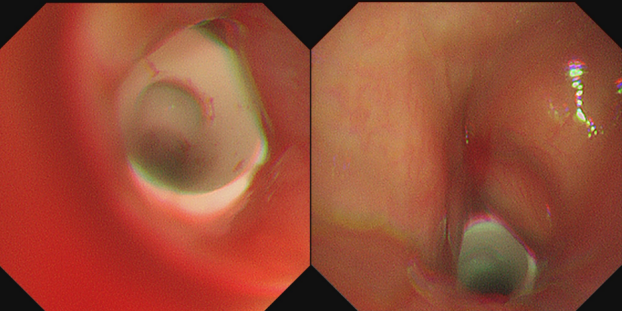

2021年10月19日,气管镜检查提示气切口上端(声门下)肉芽组织完全堵塞管腔。行冻融+冻切治疗清理管腔,术后气管镜检查见管腔通畅,效果较满意(图2)。继续其他姑息治疗方案。

图片

图2  冻融+冻切前后气管镜下表现(2021-10-19)